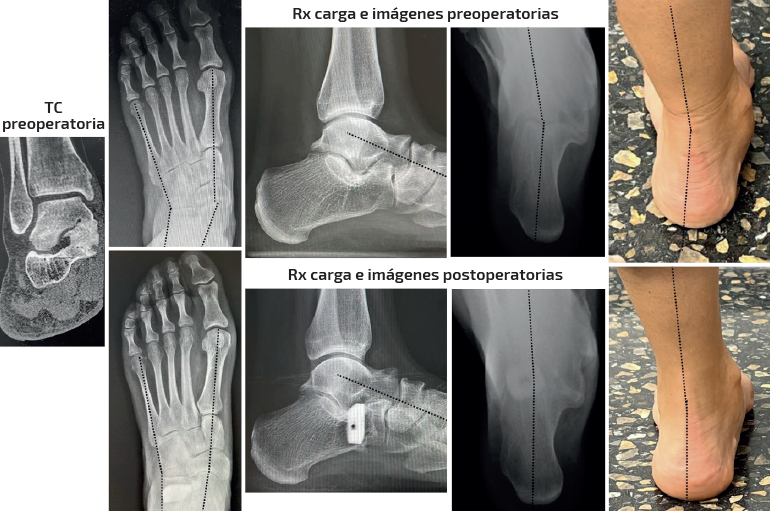

Se trata de una paciente mujer de 25 años afecta de dolor medial y sinus tarsi. Antecedente en adolescencia de esguinces laterales frecuentes. Diagnosticada previamente de forma errónea de microinestabilidad de tobillo. Evidencia de coalición ósea talocalcánea en pruebas de imagen y deformidad clínica y radiológica con predominio de abducto. Subtalar rígida. Tipo IIB de Myerson. Tratamiento: osteotomía de alargamiento de la columna externa con cuña de metal trabecular como único gesto quirúrgico. Seguimiento: 2 años. Capaz de caminar largas distancias sin dolor. Mejoría de la alineación clínica y en las radiografías dorsoplantar y de Saltzman. Sin cambios en las ángulos sagitales.